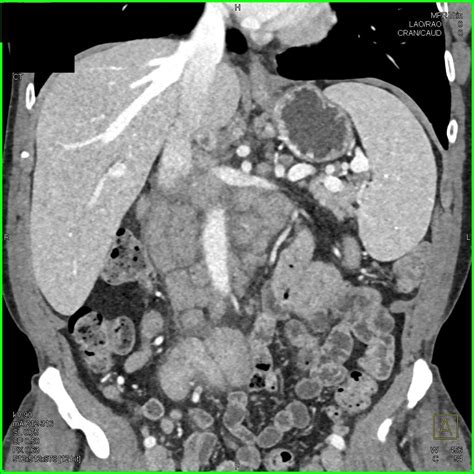

• Imaging studies: X-rays, ultrasounds, and CT scans can help visualize the intestines and detect any abnormalities.

Once a diagnosis of intestinal lymphoma is confirmed, the veterinarian will determine the stage and grade of the cancer. This information is crucial for developing an effective treatment plan.